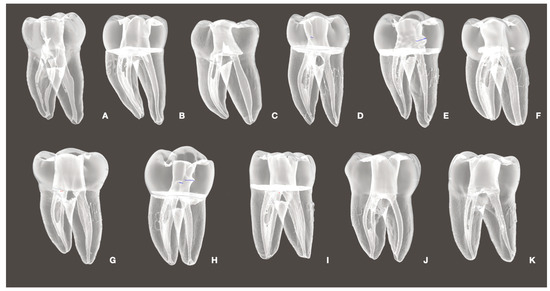

- Baasch, A.; Ramírez-Muñoz, A.; Navarrete, N.; Navarro-Candel, M.; Koury-González, J.M.; Esteves-Nieves, O.; Vieira, G.C.S.; Pérez, A.R. Influence of irrigation needle design on cleaning efficiency in 3D mandibular molar models. Odontology 2025. [Google Scholar] [CrossRef]

- Ramírez-Muñoz, A.; Escribano-Capdevila, M.; Navarrete, N.; Vieira, G.C.S.; Salamanca-Ramos, M.; Ortolani-Seltenerich, P.S.; Aranguren, J.; Pérez, A.R. Comparative Micro-CT Analysis of Minimally Invasive Endodontic Systems Using 3D-Printed Replicas and Natural Teeth. Materials 2024, 17, 5279. [Google Scholar] [CrossRef] [PubMed]